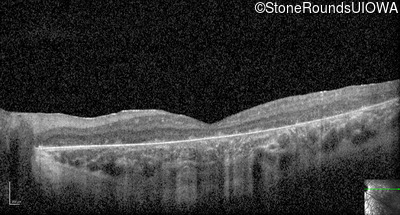

Optical Coherence Tomography - Right - 5/200

Exemplar / OCT Stack